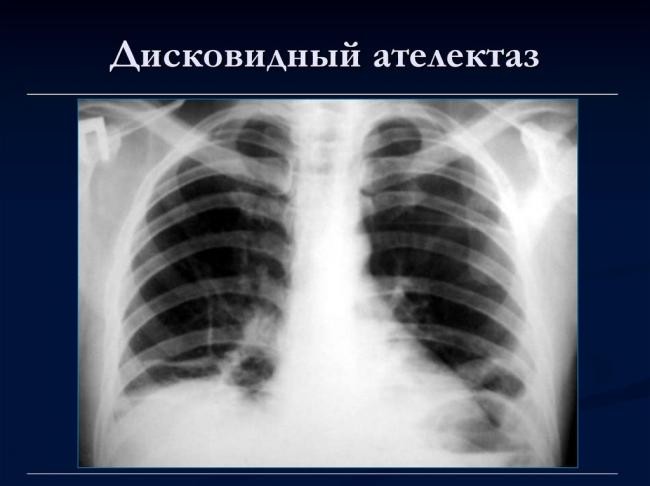

- дисковидный ателектаз – развивается на фоне сжатия нескольких долек лёгкого;

Дисковидный ателектаз легкого

Что это? Дисковидный спад паренхимы соседних долей легкого наблюдается при диффузионных патологиях бронхиального дерева, которые чаще всего вызваны пневмонитами, фиброзирующими альвеолитами, саркоидозом.

Причины могут быть различны: так, дисковидная разновидность ателектаза часто имеет компрессионную природу, т. е. развивается из-за сдавливания грудной клетки (особенно ее наддиафрагмальных областей) кровью, гноем после травмы или контузии грудной клетки.

Однородное затемнение в области поражения. Размеры тени зависят от вида ателектаза: при долевом выявляется обширное затемнение, при сегментарном — в виде клина или треугольника, расположенного вершиной к корню легкого, дольковые ателектазы множественные и похожи на очаговую пневмонию. Дистензионный ателектаз расположен низко, около диафрагмы, имеет небольшие размеры и вид поперечных полос или темных дисков. Смещение органов: при компрессионном ателектазе смещение наблюдается в здоровую сторону, так как на стороне поражения давление больше, при обтурационном, наоборот – смещение будет в сторону ателектаза, так как на стороне поражения нарастает притягивающее отрицательное давление. Подъем купола диафрагмы – это видно по расположению печени.